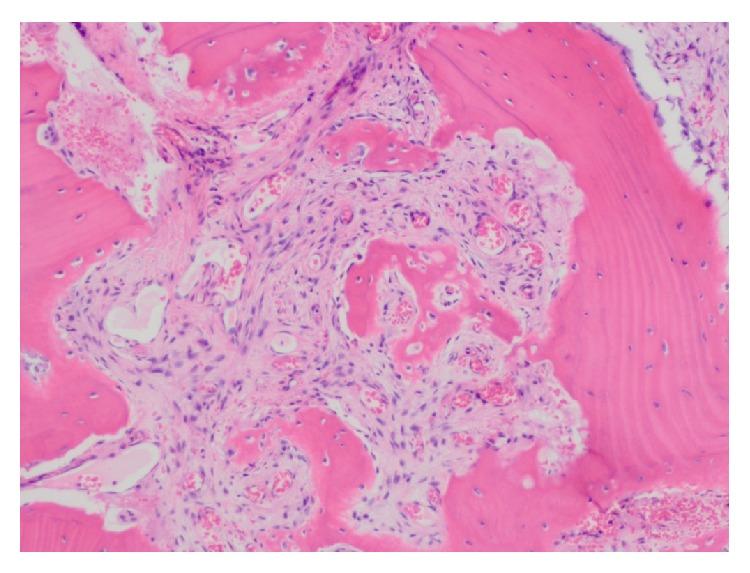

Brown tumor of hyperparathyroidism (BTHPT) is rare in the United States and not frequently seen in clinical practice. This is likely because early diagnosis and prompt treatment of this disease process prevent the progression and development of BTHPT. Conversely, BTHPT is more common in underdeveloped countries where fewer patients have access to health care and hyperparathyroidism (HPT) goes untreated. It has been reported that the incidence of BTHPT in underdeveloped countries can be as high as 58 to 69 percent in patients with primary HPT. We present a case report of a patient in the United States with a large mandibular BTHPT requiring an extensive resection in the setting of secondary HPT. Despite being rare in this country, it is important for nephrologists, primary care physicians, and oral health care providers to be able to recognize this entity, so that intervention may be rendered early.

甲状旁腺功能亢进棕色瘤(BTHPT)在美国较为罕见,临床实践中也不常出现。这可能是因为对该疾病进程的早期诊断和及时治疗可防止BTHPT的进展和发展。相反,BTHPT在欠发达国家更为常见,那里能获得医疗保健的患者较少,甲状旁腺功能亢进症(HPT)得不到治疗。据报道,在欠发达国家,原发性HPT患者中BTHPT的发病率可高达58%至69%。我们报告一例美国患者,其患有巨大下颌骨BTHPT,在继发性HPT情况下需要进行广泛切除。尽管在该国这种情况很少见,但肾病学家、初级保健医生和口腔保健提供者能够识别这一实体很重要,以便能尽早进行干预。